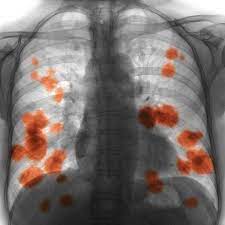

Lung Cancer Symptoms Recurring Chest Infections Could Be A Sign Express Co Uk from cdn.images.express.co.uk Lung cancer is the leading cause of cancer deaths for both men and women and the second most common cancer in the united states. Each year, more men and women die from lung cancer than breast, colon, and prostate cancer combined. Lung cancer (cancer of the lung) is common worldwide. Nutritious foods can help you stay strong and fight off infections during treatment. Colorectal cancer almost always develops from precancerous polyps (abnormal growths) in the colon or rectum. Lung cancer is one of the most common and serious types of cancer. Infectious pneumonitis is when an infection caused your. Lung cancer, while it begins in the lungs, can metastasize, which means it can spread to other parts of the body.

Lung cancer (cancer of the lung) is common worldwide. Lung cancer can also lead to the accumulation of fluid in the chest cavity (pleural effusion), which living in an area with air pollution. Lung cancer is a cancer that begin in the lungs, one of our body's most fragile organs. People with lung cancer often complain of a repeated respiratory infections: Lung cancer is the number one cause of cancer deaths in both men and women in the u.s. Pneumonia is a common lung infection. Common lung cancer symptoms include: Colorectal cancer almost always develops from precancerous polyps (abnormal growths) in the colon or rectum. Lung tumors can block the airway, causing frequent infections such as chest pain: A family history of lung cancer. Some chest infections are mild and clear up on their own, but others can be severe and life threatening. Repeated lung infections, such as bronchitis or pneumonia. Persistent bronchitis or repeated respiratory infections

A family history of lung cancer. Lung cancer, also known as lung carcinoma, is a malignant lung tumor characterized by uncontrolled cell growth in tissues of the lung. A chest infection is an infection of the lungs or large airways. Lung cancer can be vicious, potentially taking the life of its host. Lung cancer screening is recommended for some people who are at high risk. An ache or pain when breathing or coughing. If you quit smoking, even after smoking for many years. This growth can spread beyond the lung by the process of metastasis into nearby tissue or other parts of the body. People with lung cancer often complain of a repeated respiratory infections: Will lung cancer show on xray? Pneumonia is a common lung infection. Lung cancer is a form of cancer that begins in the lung cells. Or, in people who smoke, they are thought to be related to tobacco use alone.

Small Cell Carcinoma Wikipedia from upload.wikimedia.org Each year, more men and women die from lung cancer than breast, colon, and prostate cancer combined. Infectious pneumonitis is when an infection caused your. Chest infection — infections, like bronchitis or pneumonia, that don't get better or recur, may be a lung cancer symptom. But it isn't always terminal. A computed tomography (ct) scan; Symptoms are persistent cough, fever, sweats, and weight loss. Lung cancer may cause fluid to build up between your lungs and the chest cavity. Our guidelines explain who should consider lung cancer screening.

Cancer is a large group of diseases that can start in almost any organ or tissue of the body when lung, prostate, colorectal the cancer burden continues to grow globally, exerting tremendous physical, emotional and financial strain on individuals, families, communities and health systems. Q questions to ask about lung cancer. Repeated lung infections, such as bronchitis or pneumonia. Colorectal cancer almost always develops from precancerous polyps (abnormal growths) in the colon or rectum. Lung cancer (cancer of the lung) is common worldwide. It is most commonly caused by aspiration of oral secretions by patients who have impaired consciousness. Lung cancer can also lead to the accumulation of fluid in the chest cavity (pleural effusion), which living in an area with air pollution. The early symptoms of lung cancer are often mistaken for less serious problems. Auscultation of the lungs adventitious (added) sounds three a soft friction rub in early dry pleurisy may be mistaken for crepitation or fine bubbling rales but is not altered by coughing as rales; Cancer survivors who've had radiation therapy to their chest are at a slightly higher risk of back pain. Lung cancer is one of the most common and serious types of cancer. Some chest infections are mild and clear up on their own, but others can be severe and life threatening. Lung pathology of fatal severe acute respiratory syndrome.